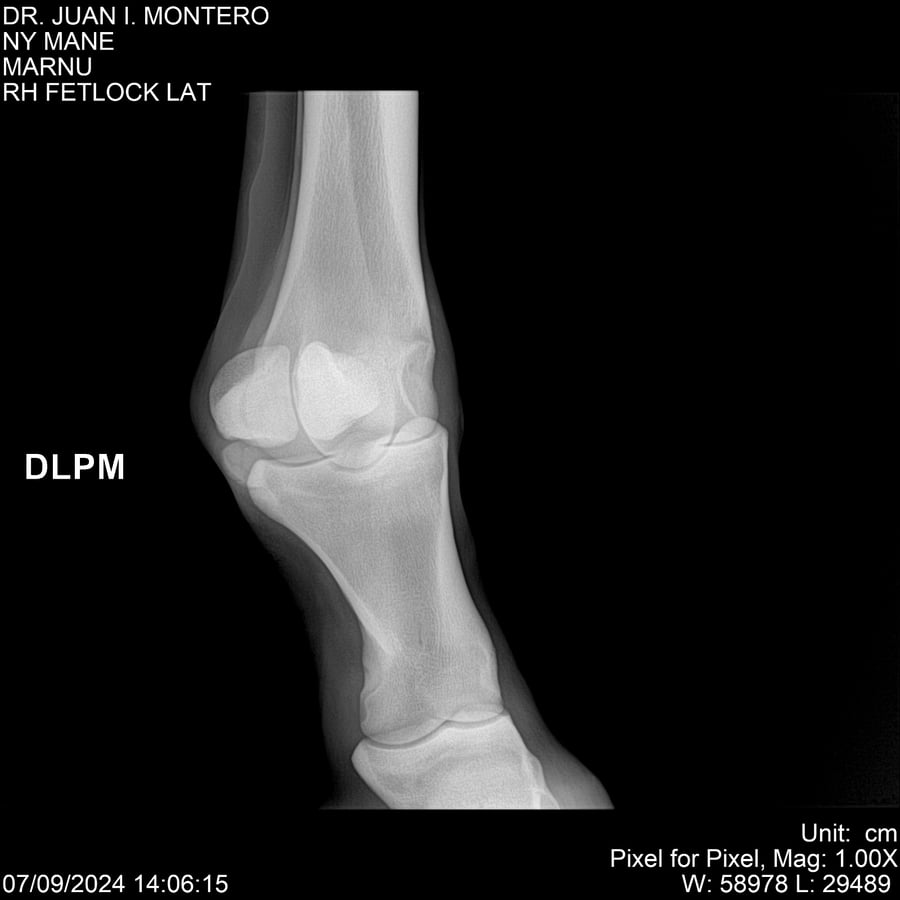

LOTE 20, NY MANE Lote Anterior Volver al remate Lote Siguiente Ficha Contacto Montevideo - Ficha del Lote Identificador: #282520 Categoría: Yeguarizos 76 Visualizaciones ClicData Contacto Empresa: Abelenda N. R., Walter Hugo Nombre*: Teléfono* : E-mail* : Mensaje Enviar Registrese gratis Este contenido Exclusivo está disponible sólo para usuarios registrados Ingresar